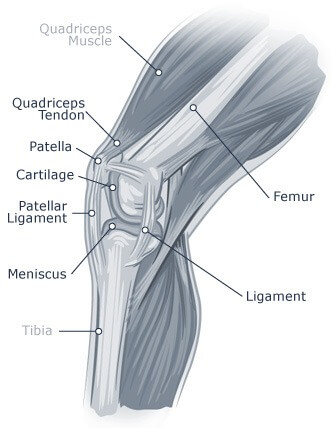

Often times, because the femur is part of the knee joint, an injury to the femur can result in knee pain. The most common injury to the femur that will cause knee pain is a distal femur fracture. Distal femur fractures are fractures that occur at the base of the femur, where it connects to the knee. This kind of fracture is common in older people, as well as those who experience high energy injuries. This type of injury can cause a misshapen knee, tenderness, swelling, bruising, and pain when pressure is put on the knee.

Quadriceps tendon tears often occur in older people who engage in running or jumping sports. These tears can be either partial or complete and often happen to people who have weakened tendons. Weakened tendons can result from tendonitis or chronic diseases like rheumatoid arthritis or chronic renal failure.

Patellar dislocation, or unstable kneecap, occurs when the patella slips out of place and becomes partially or completely dislocated, causing pain. Patellar dislocations are most often caused by blows to the knee or falls. Anyone who has suffered from a patellar dislocation may experience pain in the knee, feeling the patella slip out of place, swelling, or a distorted shape of the knee.

Cartilage is an elastic tissue that covers the ends of the long bones at the knee joint, protecting the joints and serving as a shock absorber. Although it is flexible and tough, it is still relatively easy to damage. Typically, damage to the knee cartilage is caused by direct trauma or twisting of the knee, such as from a bad fall, auto accident or direct blow to the knee during sports activities. Age-related wear and tear as well as a lack of mobility can also cause damage, as our joints need regular movement to remain fluid and healthy.

The patellar tendon extends down from the patella bone to the tibia. Patellar tendon tears can be either partial or complete and are often caused by jumping or falling injuries, patellar tendon weakness (caused by patellar tendonitis or chronic diseases that disrupt blood supply), or previous surgery around the tendon. Symptoms may include an indentation at the bottom of the kneecap, difficulty walking, tenderness, mobility of the patella (which is no longer secured to the tibia).

The meniscus are the two pieces of cartilage between the femur and tibia (singularly pronounced menisci). They cushion the bones from the impact that accompanies exercises such as walking, running and jumping. Meniscus tears are often the result of high impact athletic injuries. People who experience a menisci tear may feel a pop when the tear actually occurs. Afterwards there may be pain, swelling, or immobility of the knee.

Knee ligament injuries are extremely common, especially amongst athletes involved in contact sports like football and basketball. However, these injuries can happen to anyone at any age. Often times, ligament tears occur from changing direction suddenly or twisting while engaged in physical activity.